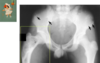

Describe the X-ray appearance of osteosarcoma

- Usually metaphyseal

- Lytic

- Permeative

- Elevated periosteum (Codman’s triangle)